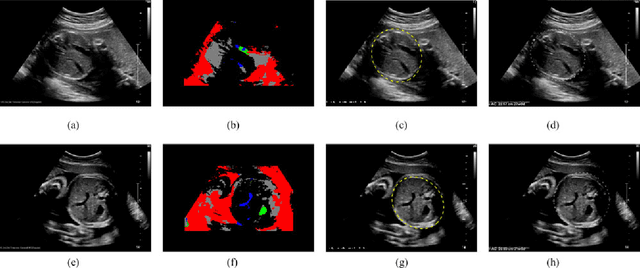

Abstract:Ultrasound diagnosis is routinely used in obstetrics and gynecology for fetal biometry, and owing to its time-consuming process, there has been a great demand for automatic estimation. However, the automated analysis of ultrasound images is complicated because they are patient-specific, operator-dependent, and machine-specific. Among various types of fetal biometry, the accurate estimation of abdominal circumference (AC) is especially difficult to perform automatically because the abdomen has low contrast against surroundings, non-uniform contrast, and irregular shape compared to other parameters.We propose a method for the automatic estimation of the fetal AC from 2D ultrasound data through a specially designed convolutional neural network (CNN), which takes account of doctors' decision process, anatomical structure, and the characteristics of the ultrasound image. The proposed method uses CNN to classify ultrasound images (stomach bubble, amniotic fluid, and umbilical vein) and Hough transformation for measuring AC. We test the proposed method using clinical ultrasound data acquired from 56 pregnant women. Experimental results show that, with relatively small training samples, the proposed CNN provides sufficient classification results for AC estimation through the Hough transformation. The proposed method automatically estimates AC from ultrasound images. The method is quantitatively evaluated, and shows stable performance in most cases and even for ultrasound images deteriorated by shadowing artifacts. As a result of experiments for our acceptance check, the accuracies are 0.809 and 0.771 with the expert 1 and expert 2, respectively, while the accuracy between the two experts is 0.905. However, for cases of oversized fetus, when the amniotic fluid is not observed or the abdominal area is distorted, it could not correctly estimate AC.